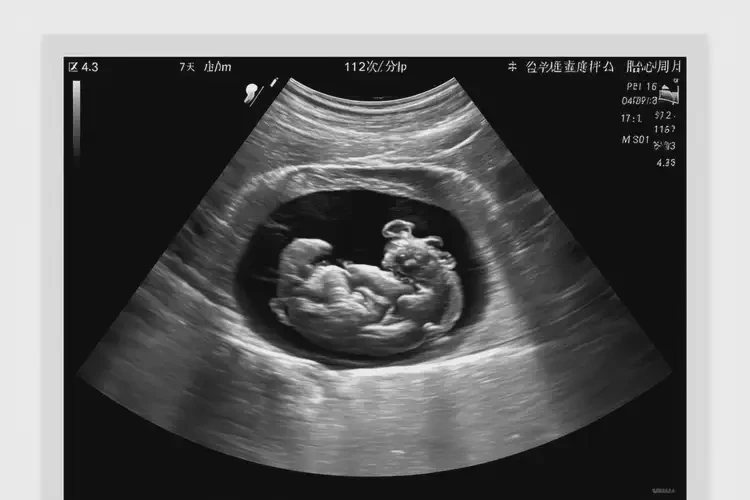

孕7周3天胎心112正常嗎

112次/分鐘

在孕7周3天時(shí),胎心112次/分鐘 屬于正常范圍。胎心率的正常范圍通常在 110-160次/分鐘,個(gè)體差異和測量誤差可能導(dǎo)致胎心率在一定范圍內(nèi)波動(dòng)。

孕7周3天胎心112正常嗎(圖1)